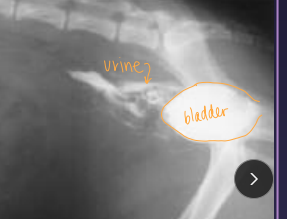

Dt: HCBC/chem (infection, azotemia), rads (loss of serosal detail), abdominocentesis (fluid Cr & K > blood levels), contrast cystourethrogram

Creatinine, potassium – higher than peripheral blood